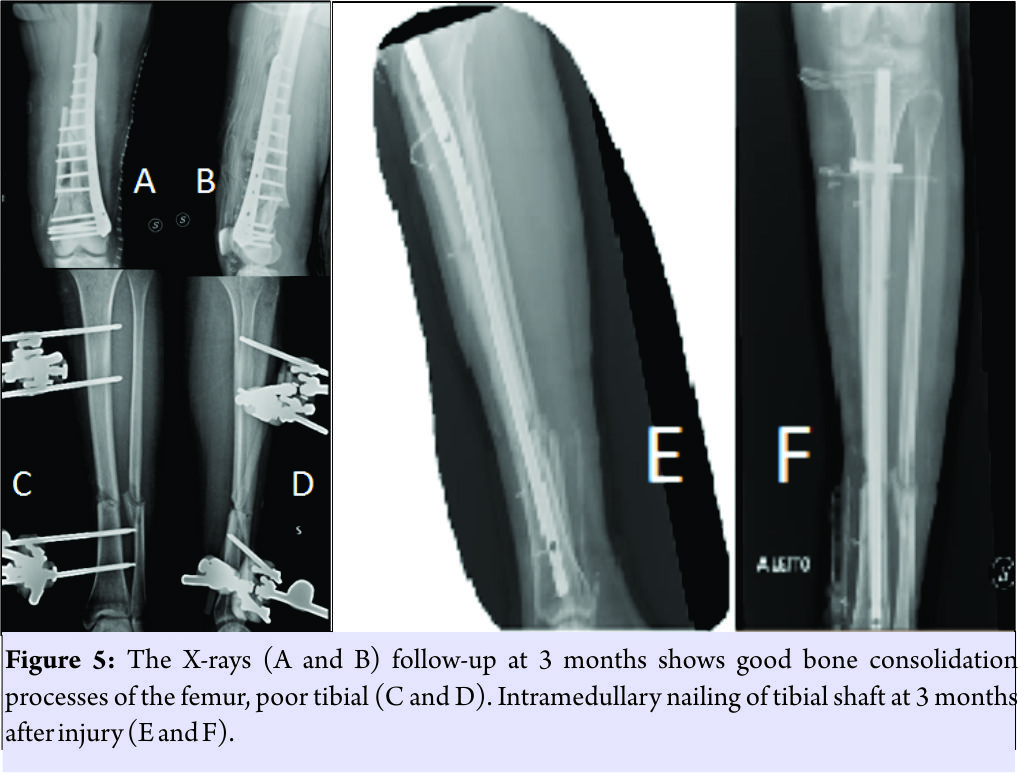

The patient was treated in emergency with a bridge femorotibial external fixator after extensive cleaning and debridement of open fractures(Fig.3a and b). After stabilization, the wounds were covered with iodine-impregnated incision drape (Ioban). During the damage control’s operations, a fragment of 8 cm × 3 cm × 4cm of bone substance corticospongiosa was found in the left sock. The fragment was immersed in a solution of cefuroxime, gentamicin, and metronidazole and maintained at a temperature of −3°C until 2h before the intervention because it was irradiated with a dose of 25kGy. The 4days, we removed the antibiotated chains and the Ioban cover which were replaced with vacuum therapy. The patient never had fever over 38°Cduring his 10 days in intensive care and in the ward. The delayed risk of tibial consolidation was equal to 8 of 10 according to A.R.R.C.O. As regards the femur, the risk of non-union of the fracture of the femur of 51 points according to the non-union scoring system(N.U.S.S). The patient was not treated surgically for the fissure of the spleen, and the resolution of the neurological picture took place after 6 days. The patient was submitted to a specific antibiotic therapy according to the protocol for the open fractures and was monitored with clinical and laboratory examinations. The 21stday post-trauma, without any clinical or laboratory signs, the patient was operated on with a less invasive stabilization system plate and screws, cortical and cancellous bone grafting allogeneic bank, and autologous stem cells taken from the iliac crest, PRP rich in leukocytes and replanting of native bone. The surgical access chosen was the lateral subvastus to preserve the perforating arteries(Fig.4). The patient was monitored with 15 days clinical follow-up, laboratory, and radiological at 1 month, 2 months, 3 months, 6 months, 12 months, 18 months, 24 months, 36 months, and 48 months. The indices used to evaluate the outcomes of this intervention were the knee injury and osteoarthritis outcome score (KOOS), the related union scorefemur (R.U.S.F.) for the femoral bone healing, and the score radiographic union score for tibial fractures (R.U.S.T.). For bone consolidation of shank, the short form 12 health survey (SF-12) for the quality of life, and the number of complications and re-operations. The patient in the immediate post-operative made active and passive mobilization of the knee until the 3rdmonth, reaching a flexion of 90°. The patient was subjected to the intervention of removal of the external fixator and intramedullary nailing of the tibia 3 months after the first surgery(Fig. 5).

The patient was not treated surgically for the fissure of the spleen, and the resolution of the neurological picture took place after 6 days. The patient was submitted to a specific antibiotic therapy according to the protocol for the open fractures and was monitored with clinical and laboratory examinations. The 21stday post-trauma, without any clinical or laboratory signs, the patient was operated on with a less invasive stabilization system plate and screws, cortical and cancellous bone grafting allogeneic bank, and autologous stem cells taken from the iliac crest, PRP rich in leukocytes and replanting of native bone. The surgical access chosen was the lateral subvastus to preserve the perforating arteries(Fig.4). The patient was monitored with 15 days clinical follow-up, laboratory, and radiological at 1 month, 2 months, 3 months, 6 months, 12 months, 18 months, 24 months, 36 months, and 48 months. The indices used to evaluate the outcomes of this intervention were the knee injury and osteoarthritis outcome score (KOOS), the related union scorefemur (R.U.S.F.) for the femoral bone healing, and the score radiographic union score for tibial fractures (R.U.S.T.). For bone consolidation of shank, the short form 12 health survey (SF-12) for the quality of life, and the number of complications and re-operations. The patient in the immediate post-operative made active and passive mobilization of the knee until the 3rdmonth, reaching a flexion of 90°. The patient was subjected to the intervention of removal of the external fixator and intramedullary nailing of the tibia 3 months after the first surgery(Fig. 5). The patient has walked with a partial load up to 6 months after the injury and then began to progress to a total load. At 12 months, the patient had a KOOS of 89.3 points, a SF-36 of 89.3 points, the R.U.S.T. 3 out of 3 points, and R.U.S.F. 3 out of 4 points. At 24months, the patient had an intramedullary nail removal of 100 points KOOS, 100 points SF-36, the R.U.S.T. 3 out of 4 points, and R.U.S.F. 4 out of 4 points. At follow-up at the past 36 months, a year after the removal of plaque and nail, the patient showed KOOS 100 points, a SF-36 out of 100 points(Fig. 6), and R.U.S.T and R.U.S.T 4 out of 4 points(Fig. 7). After 2 years, the patient had the tibia nail removed. The patient did not present any complications throughout the post-operative and follow-up.

The floating knee is unfortunately always associated with more internal injuries that make it difficult to provide a total care early on [6]. Furthermore, in our case, we had a double IIIB exposure which is very rare in floating knee IIB according to Fraser. Looking at the ISS score and the GCS, we must put a damage control in place [7], before the stabilization of both bone fragments, it is essential to carry out a careful debridement and thorough washing with a physical examination of the exposition. As reported by Veith, to have a chance of a good outcome, and also to save the patient’s life and reduce perioperative complications, it is necessary to optimally stabilize both segments. In fact, our choice fell on the external fixation, putting the knee bridge in bending at 20°. To maintain the highest possible sterility and preserve the sites of exposure by superinfection of resistant super bacteria residing in TI, we have isolated the bone exposure with a steri-strip with betadine [8] waiting to activate the vacuum-assisted closure (VAC) therapy at the moment not yet available at our structure. As shown by Grubor et al. [9], the use of VAC therapy in open fracture IIIB Cierny and Mader IIIB osteomyelitis drastically reduces the risk of septic shock and limb amputation. In the literature, there are not many studies, but a few case reports show the opportunity to replant large fragments of bone devascularized, however, to make this replanting on final osteosynthesis you need to make careful cleaning and debridement. The bone fragment was sent to the bone bank for a proper preservation and thawed 2 days before, to be subjected to a treatment for decantation in antibiotics and irradiation with ionizing rays to avoid the formation of bacterial biofilms on the surface of the implant. The treatment by decantation in the three antibiotics was fundamental: Gentamicin for the broad spectrum against g + and g − bacteria, in particular against Escherichiacoli, coliforms, Pseudomonas aeruginosa, and Proteus [10] and for the ability to perform a surfactant function that covers the bone surface and prevents the adhesion of bacterial colonies [11]; cefuroxime, also for the broad spectrum of action and in particular the activities toward all Staphylococci and Streptococci and metronidazole for the activity to all anaerobes as Freeman et al. [12].In the literature, there is no consensus on how to permanently sterilize bone segment to replant, however, Singh et al. [13] showed the high rate of sterilization of tumor cells from soft tissue using the autoclave. However, the use of the autoclave to the high temperatures destroys the osteoinductive capacity and mechanical bone to replant [13]. According to ISO 11137, 2002 to sterilize the bone serve a 25 kGy of ionizing rays, in fact, Aizah et al. [14] showed a success in the replanting of a distal femoral metaphysis (open fracture IIIA GA) in a young man of 14 years after sterilization by gamma irradiation of the entire fragment. Finding ourselves in front of a massive bone loss >50% of the distal metaphysis of the femur and a N.U.S.S score of 51, we had to resort to diamond concept, being comparable to a Grade 3 N.U.S.S, or rather compromission of both biological and mechanical segments. We decided, even in the absence of inflammatory or septic manifestations, to wait 21 days for the final intervention, as a soft callus was formed which is comparable to a primordial biological room. At the same time, the necessary time for the formation of our biological room with respect to the distal femur had relapsed; we had to choose among three possible treatments: The method of pseudomembrane of massequet, the double opposed plate of metal according Ruedi, and the organic metal solution according to the Bologna’s school. The choice of the method was carried out in the surgery room, after the subvastus lateral access for the preservation of the perforating [15], and therefore, the respect of the biology of the lateral compartment. It was decided to opt for the organic metal solution, as from the experience of periprosthetic femoral fractures, the contrast between a splint bone and a metal plate increases the mechanical strength of the femur 2250 N and is the best biological solution, considering that the splint has a mechanical filler as well as a stimulus for the bone’s growing [16]. Our technique has been put in place respecting the algorithm devised by Calori et al. [17], with the only change the PRP and mesenchymal cells instead of Bone morphogenetic protein-7, for exploiting the totipotent capacity of leukocytes to turn into osteoblasts [17]. Having a ligament stability from both the collaterals and cruciates, and because we did not have a fibrous retraction, nor a knee pseudoankylosis since the early moments of the intervention, we made a cautious passive knee kinesis with a progressive increase of joint range of motion during the post-operative days. The external fixator leg during surgery had been overhauled by placing compression fragments to heal the fracture of tibia with that kind of synthesis. We scored ARCO and could see both direct and indirect radiological signs of modest bone callus, 3 months after, the tibia had been repaired with plate and screws, to increase the partial load bearing ability, the patient had been able to progress to total load bearing; there were also direct and indirect bone regeneration and strengthening of the femur that allowed the patient to walk with aids. Although trivial, we were able to ascertain that the mood of the patient was directly related to the ability to walk that was gradually acquired [18]. The clinical and radiographic results in the case reported are certainly encouraging, demonstrating that at least part of the “biological push” provided by the use of stem cells is capable of increasing the potential of synthesis techniques, however, we should not underestimate the opportunity to attack the biological chamber through the soft tissue and the possible role of the post head trauma somatostatin secretion that may assist the regenerative potential of stem cells. Furthermore, the placement of a splint to the medial cortical bone level opposite to the plaque leads to an increase of the resistance of the femoral medial wall to almost 2250 Newton giving the femoral shaft undisputed biomechanical advantages. These results encourage a continuation of the experience and a comparison with the literature for results that are uniform for each one.